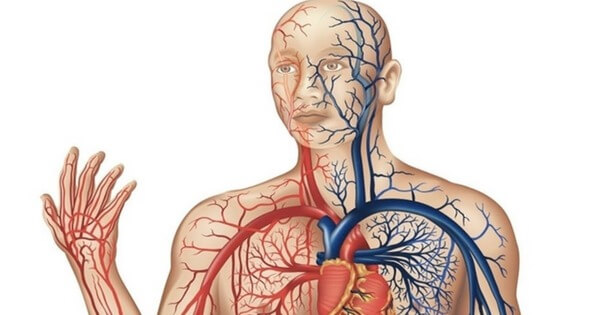

O sistema circulatório é responsável pelo transporte de sangue e inúmeras moléculas para o corpo, como o ferro e o oxigênio. Este sistema é composto pelas artérias, os capilares e as veias.

As veias do corpo humano são um dos tipos de vasos do sistema circulatório. Elas são distribuídas por todo o corpo e sua principal função é distribuir o sangue pobre em oxigênio até o coração.

As principais veias do corpo humano são: